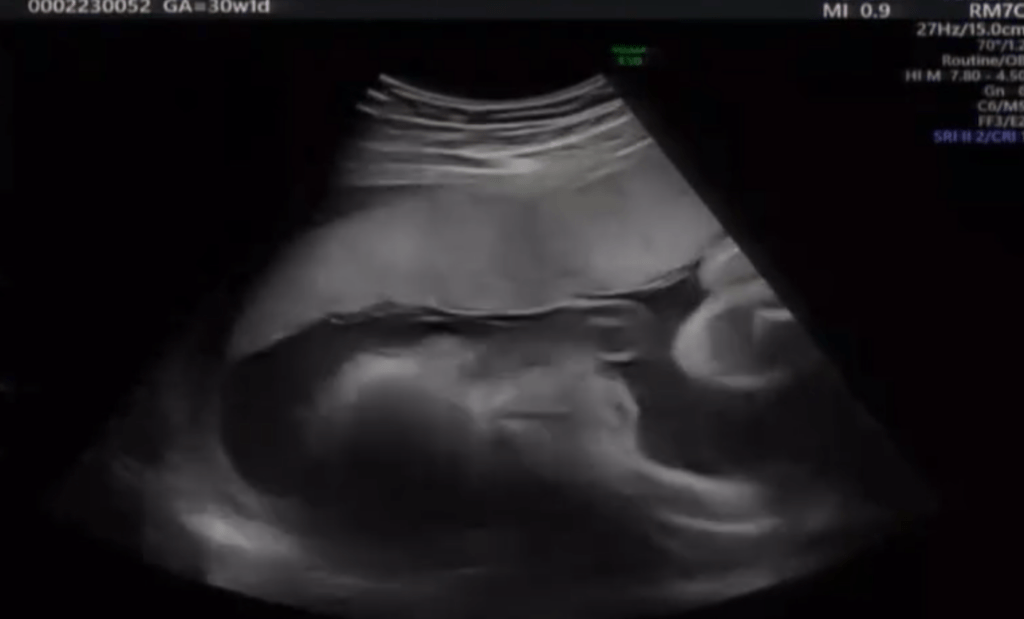

• 風邪をひいた1歳息子。病院に行くと…医師「間違いなくガンですね」即入院が決まり5年、現在の様子に迫る